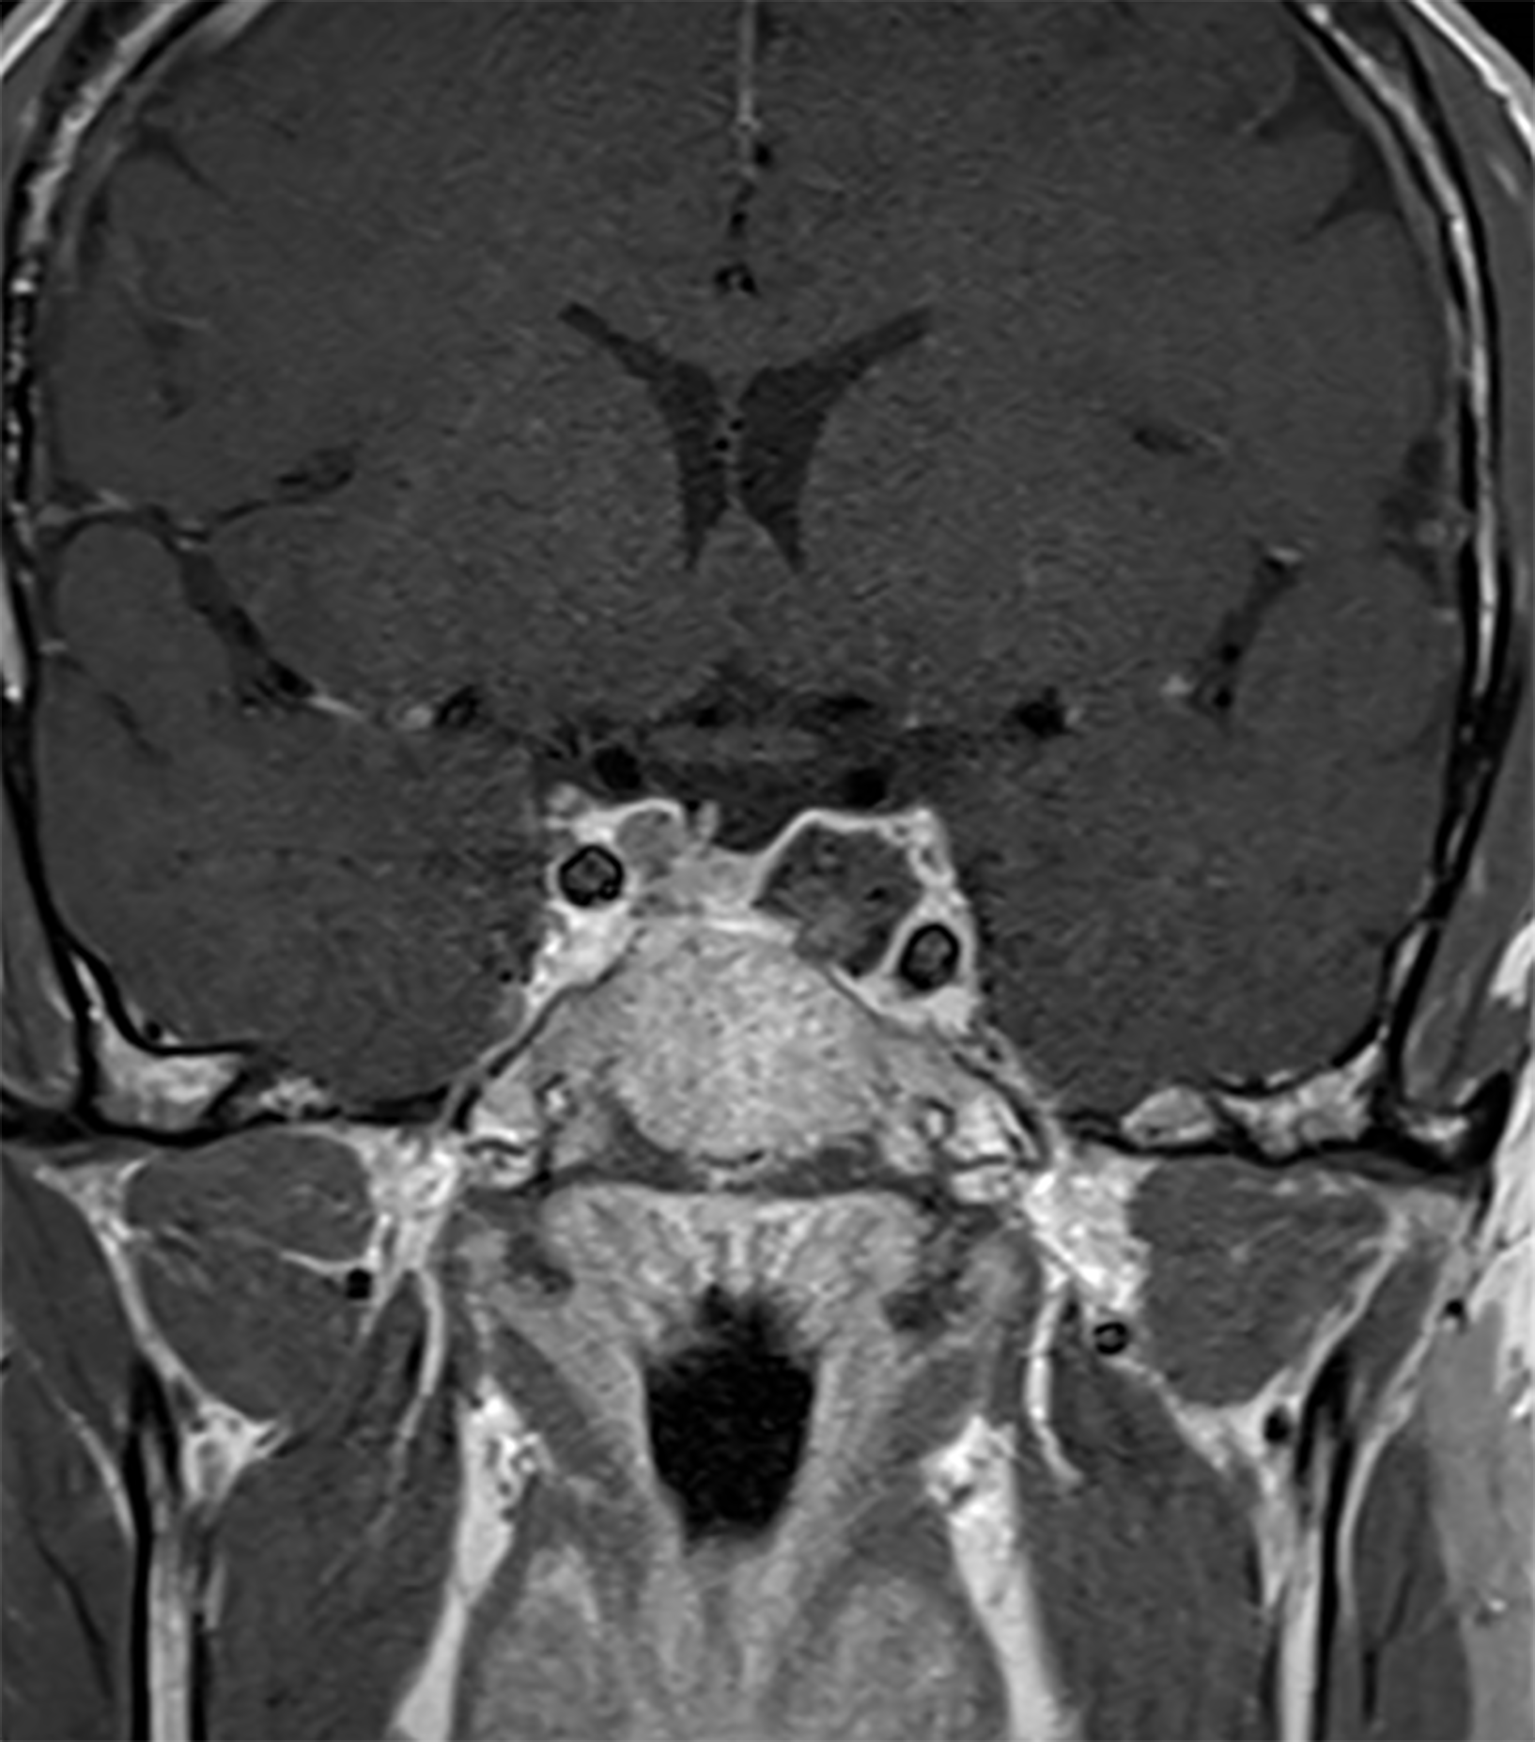

The patient was then operated using an endoscopic endonasal transsphenoidal approach to remove the tumor and decompress the structures inside the cavernous sinus (19). Intraoperatively, we found hemorrhagic areas and blood clots inside the tumor which confirmed the diagnosis of apoplexy. Histopathological analysis revealed the presence of a clinically silent sparsely granulated corticotroph adenoma. There was no hormonal co-expression detected. Post-operatively, third cranial nerve palsy resolved Figure 1. His post-operative work-up showed mild/moderate corticotrope deficiency and the patient was temporarily substituted with hydrocortisone. Subsequent pituitary retesting at 6 weeks post surgery confirmed normalized corticotrope function (ACTH-stimulation testing) and reversal of the hypogonadotropic profile in the presence of normal testosterone levels Table 1. Immediate postoperative MRI showed no residual tumor Figure 3. Given the absence of residual tumor, we did not perform a screening for subclinical hypercortisolism (such as a low-dose dexamethasone suppression test) after the surgery. Serial monitoring of cortisol and ACTH levels is scheduled.

Figure 3

Post-operative MRI. Sagittal MR Imaging T1 with Gadolinium showed a total resection of the pituitary adenoma.